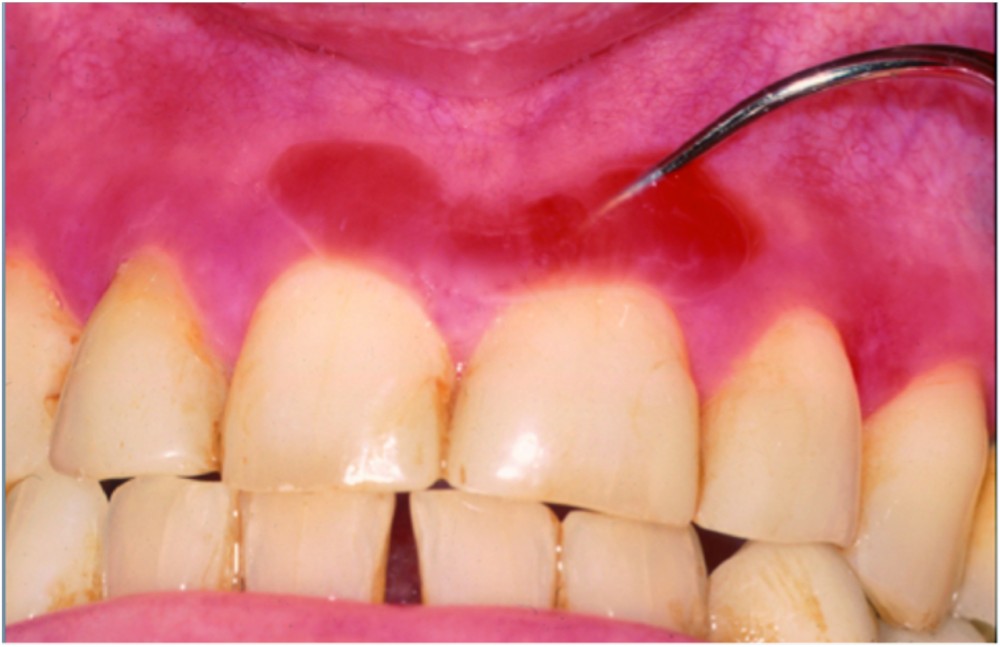

Il existait un érythème diffus mais irrégulier, intéressant la fibro-muqueuse gingivale vestibulaire, surtout supérieure. L’érythème, peu marqué, n’était pas limité au bord libre de la gencive et pouvait toucher la fibro-muqueuse sur toute sa hauteur. Dans la région médiane supérieure, on observait une large bulle avec un contenu hémorragique.

La biopsie et l’examen en immunofluorescence directe ont confirmé le diagnostic de pemphigoïde cicatricielle des muqueuses.

Synthèse. La pemphigoïde cicatricielle des muqueuses est une maladie bulleuse auto-immune qui touche principalement la fibro-muqueuse gingivale, surtout chez des femmes âgées. Elle est souvent initialement considérée comme une banale gingivite. En phase d’activité, on peut observer un dépôt blanchâtre au collet des dents correspondant à un exsudat fibrineux. Comme ce dépôt se forme rapidement et qu’il ressemble à de la plaque, les patients sont régulièrement accusés d’être responsables de leur gingivite en raison d’une hygiène bucco-dentaire insuffisante. L’examen microscopique montre un décollement sous-épithélial avec un dépôt linéaire d’IgG et de C3 sur la membrane basale. Il existe une dizaine d’antigènes-cibles, mais le plus fréquent est le BPAg2 de 180 kD. Il faut systématiquement…